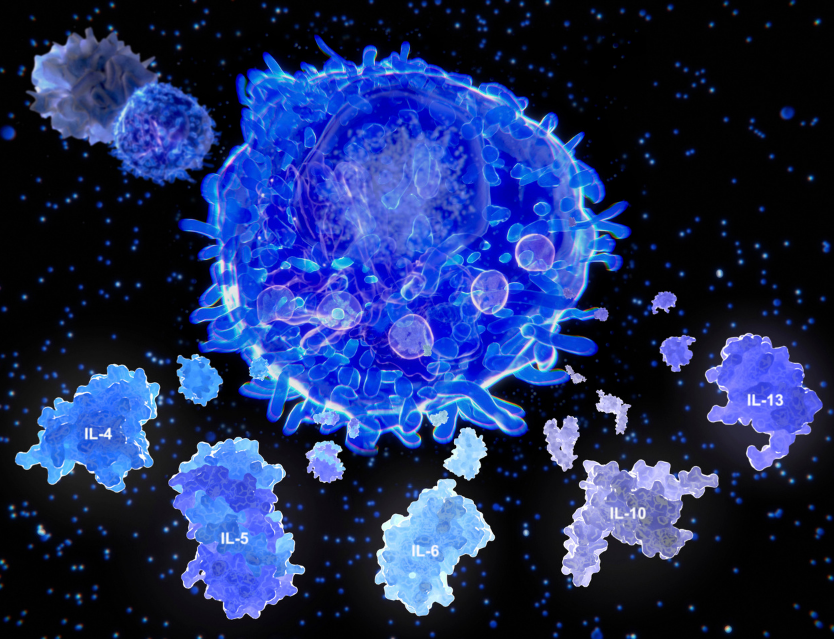

La HIPEREMIA MECÁNICA es uno de los efectos de la técnica, consiste en un aumento del riego sanguineo y como consecuencia un aumento de oxígeno y de nutrientes en la zona irrigada. Por otro lado, con el tratamiento se eliminarán gracias también a esta hiperemia, los metabolitos de desecho del proceso inflamatorio generados en la zona de lesión.

Otro efecto imporante es la propia MOVILIZACIÓN que se genera en la técnica. El mantenimiento de la movilidad del tejido lo libera de adherencias generadas por el fibrinógeno propio del proceso inflamatorio y mejora al mismo tiempo, las posibles cicatrices ocasionadas por las microlesiones del daño en el tejido.

Como otros efectos suplementarios podemos añadir la eferencia a través del estímulo de mecanoreceptores que discurren a través de una vía nerviosa de transmisión más rápida a nivel médula-tálamo, generando una analgesia (gate control system o bloqueo de la puerta de entrada).